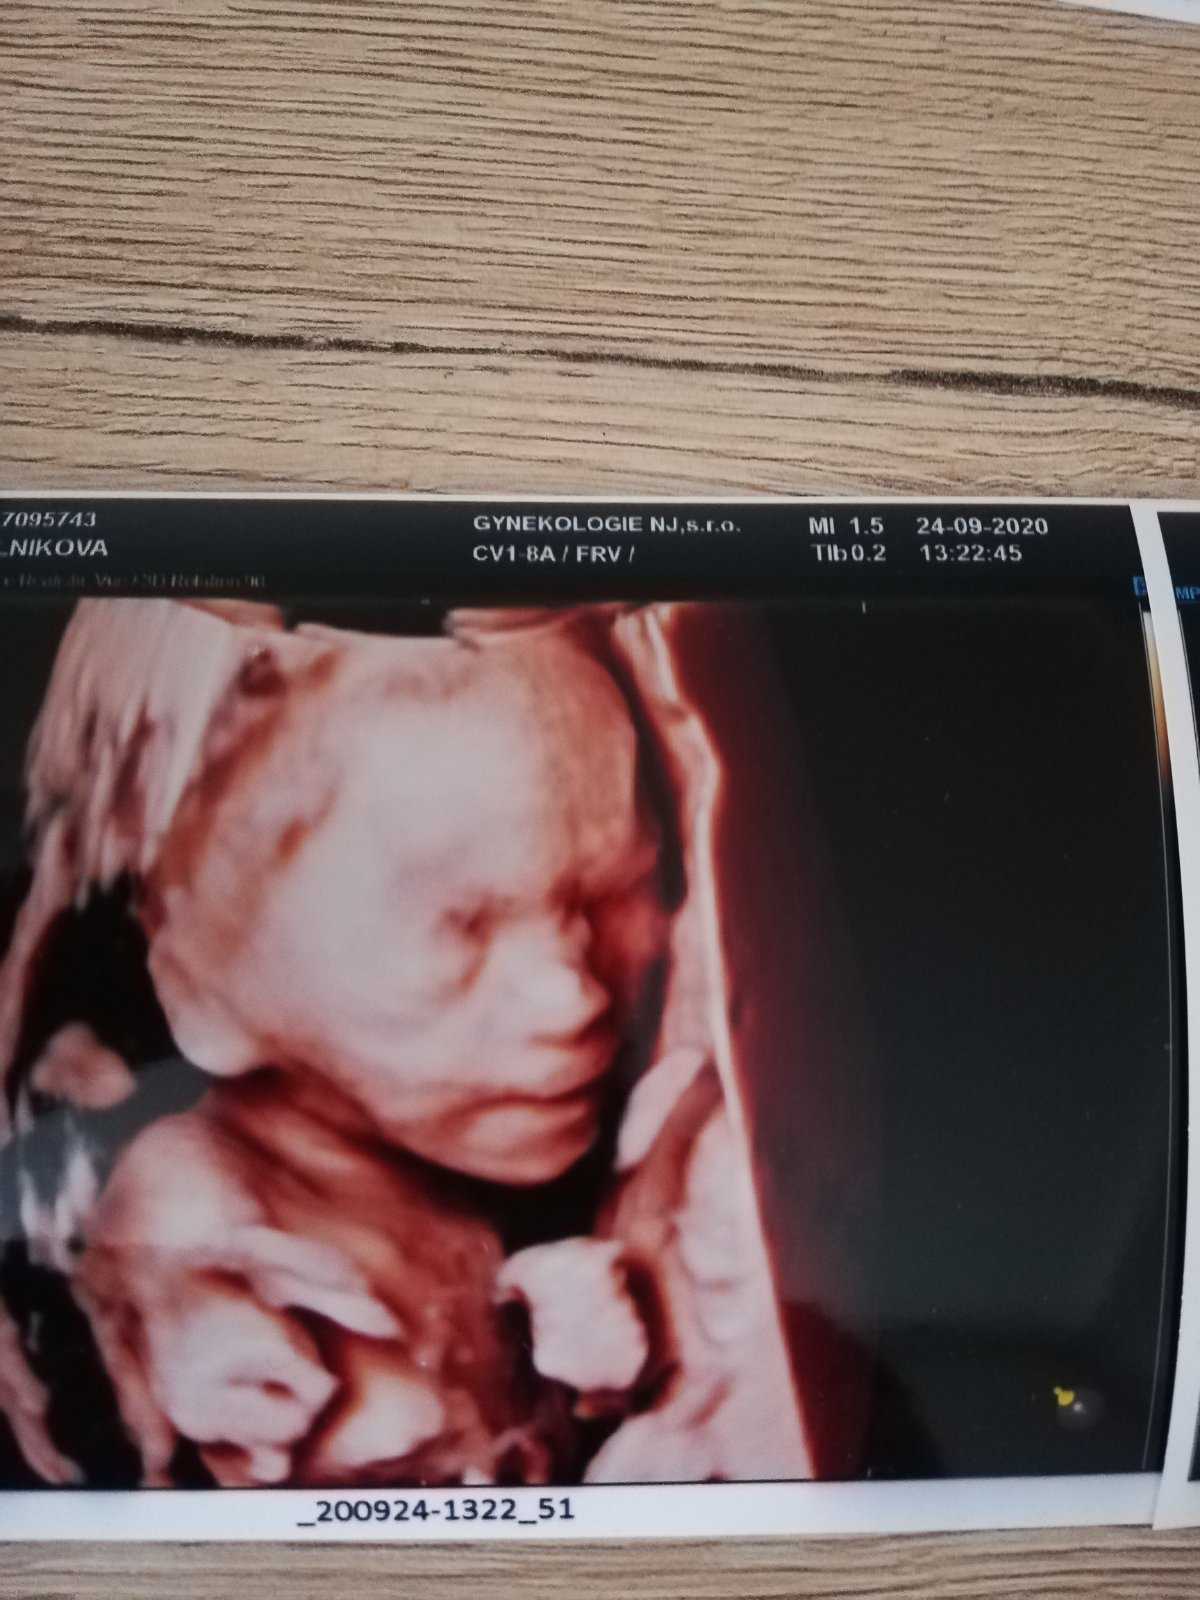

@juliemichal Ty už plánuješ páté kolo😂. Teď v předposledním dílu pořadu Malé lásky se měl taky narodit několikrát potvrzený chlapeček a narodila se holčička 😄. Já už toto těhotenství prožívám těžce a už nechci 😂. Doktor u mě na 3d nakonec řekl chlapeček taky, ale byl to boj 😲. Ještě jdu na velký ultrazvuk a pořád doufám že se pletou 😁

@pavlinkadv Ta moje fotka je z 21. týdne a pohlaví tam je 😉